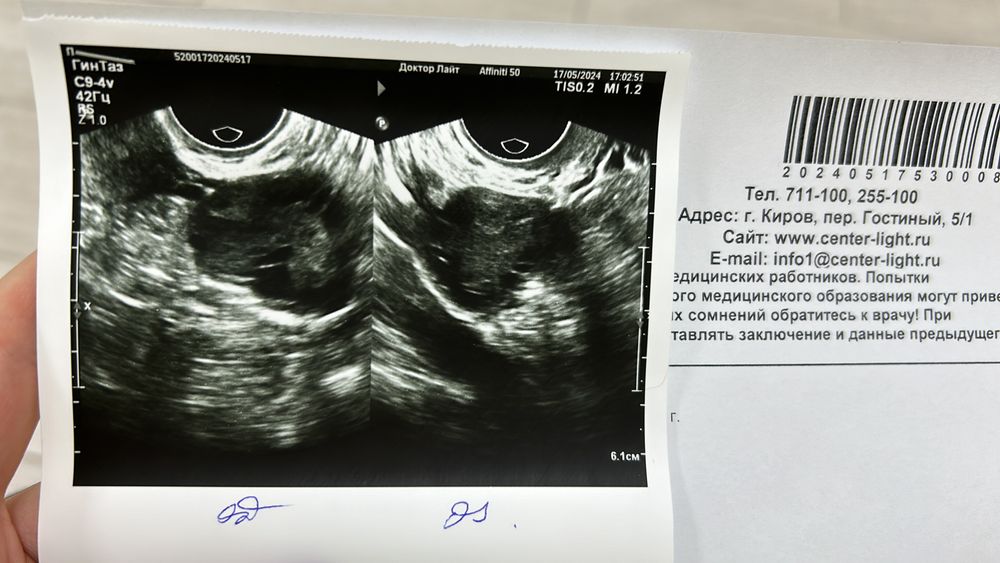

Всем привет. Планируем беременность 8 месяцев. своей овуляции не было все это время, но тут случилось чудо и была своя овуляция, но ушла в кисту жт 6см. Врачи говорили что рассосется за 2-3 цикла

Получается сегодня 11 день цикла (первый цикл еще), узистка говорит кисты нет. Как такое возможно? Прикрепила фото, может кто-то понимает? Как будто киста есть(